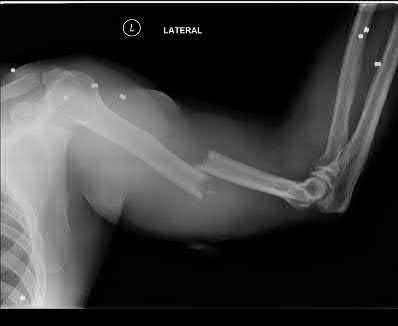

A 12-year-old male sustains an ulnar fracture with an associated posterior-lateral radial head dislocation. After undergoing closed reduction, the radiocapitellar joint is noted to remain non-concentric. What is the most likely finding?

In pediatric Monteggia fractures the annular ligament is commonly interposed in the radiocapitellar joint.

Bado initially described and classified Monteggia fractures. The most common injury pattern is an extension type 1 with anterior radial head dislocation and apex anterior ulnar shaft fracture. The apex of the ulna fracture determines the direction of the radial head subluxation or dislocation. Adults typically require ORIF of the ulna. These fractures in children are often treated non-operatively with closed reduction if the ulna fracture is transverse and stable. Type III is the one most commonly associated with irreducibility of the radial head because of interposition of the annular ligament. The incidence of posterior interosseous nerve injury is high with this lesion. The nerve deficit usually completely resolves rapidly and spontaneously.

Tan et al reviewed their treatment of 35 children with Type I and Type III Monteggia fractures. All radial heads were explored and the interposed annular ligament was stretched out of the joint space. They noted that none of the patients had any recurrent dislocation or subluxation.

Ring et al in their review stress the importance of an anatomic reduction of the ulna to restore the reduction of the radial head.